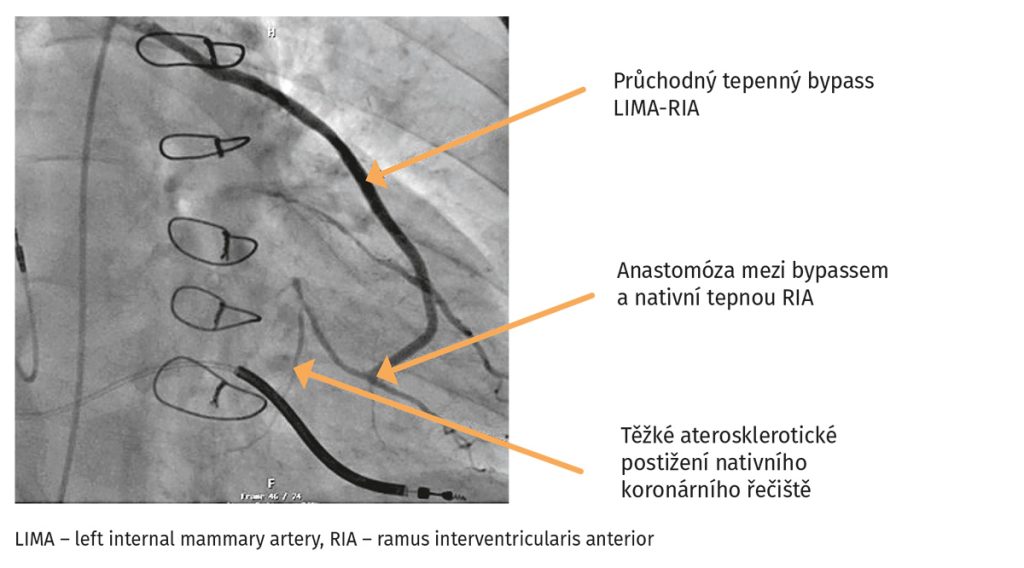

Laboratorní vyšetření ukázalo zvýšení koncentrace NT-proBNP na 1904 pg/ml, koncentrace kreatininu byla 106 µmol/l, odhad glomerulární filtrace 60 ml/min/1,73m2. Koncentrace hemoglobinu byla normální 157 g/l, kalemie byla 4,7 mmol/l, natrium 137 mmol/l. Provedená transthorakální echokardiografie ukázala pokles EF LK na 25 %. Po dohodě s pacientem byl změněna farmakoterapie – přerušena léčba ramiprilem a nově indikován sakubitril/valsartan v úvodní dávce 49/51 mg dvakrát denně a dále inhibitor SGLT2 empagliflozin v dávce 10 mg denně. U pacienta byl indikována elektrická kardioverze a rekoronarografie. Rekoronarografie prokázala průchodné bypassy bez výraznější progrese koronární aterosklerózy nativních tepen (obr. 4). Pacient podstoupil úspěšnou elektrickou kardioverzi na sinusový rytmus, respektive sekvenční stimulaci kardioverterem-defibrilátorem (ICD). Ta se jevila jako nevýhodná při stimulaci pravé komory, proto bylo u pacienta rozhodnuto o indikaci k fyziologické kardiostimulaci (stimulace převodního systému). Byl proveden takzvaný ,,upgrade“ stimulačního systému, kdy třetí elektroda je zaváděna do oblasti levého Tawarova raménka, a nahrazuje tak klasickou srdeční resynchronizační léčbu (se zavedením elektrody pro levou komoru cestou koronárního sinu a větví vena cordis magna s následnou synchronizací levé a pravé komory). Elektrokardiografie po elektrické kardioverzi a zavedení raménkové stimulace ukazují pravidelnou sekvenční síňokomorovou stimulaci ze zúžením šíře QRS komplexu (obr. 5).

Obr. 4 Koronarografie u pacienta se zhoršením srdečního selhání